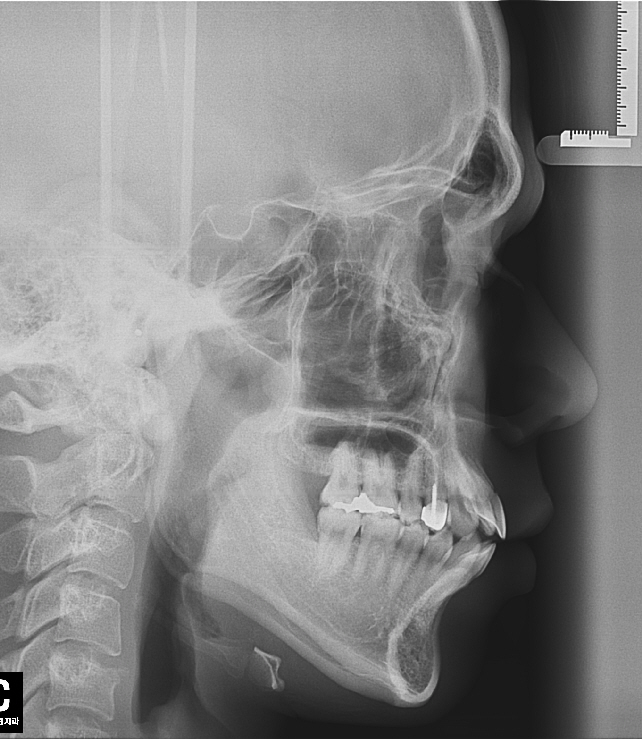

뻐드렁니(개방교합)와 돌출입을 해소하기위해서 교정 결심했습니다

그래서 인비절라인으로 결정하고 돌출입을 해소하기위해서 발치로 진행하려했는데, 인터넷 커뮤니티나 다른 병원에서 인비절라인 발치 교정은 효과를보기 힘들다고하더군요 돌출입을 개선하기위해서는 발치가 동반돼야하는데 인비절라인이라는 장치가 아직 완전하지않기때문에 발치를 동반한교정은 다른 교정장치를 사용하라고하더군요 어떤 치과에서는 인비절라인 발치교정 성공사례는 저널에실릴정도로 좋은 사례가 희박하다는데 사실인가요?

사진은 제 치아상태입니다. 좋은말씀부탁드립니다